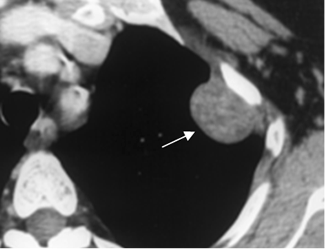

Fig 43. Lesión extrapelural.

TAC axial. Imagen sólida en relación con el arco costal, que corresponde a neurofibroma.